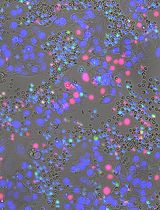

The CYTO-ID® Autophagy Detection Kit used in this protocol contains a green dye that has been optimised by identifying titratable functional components that allow minimal staining of lysosomes while showing bright fluorescence when incorporated into pre-autophagosomes, autophagosomes, and autolysosomes. The kit also contains Hoechst dye for nuclear staining to enable the detection of autophagosomes per nucleus. In addition, the lysosomal inhibitor chloroquine can be added as a positive control. By inhibiting lysosomal degradation, the autophagosomal process is interrupted and autophagosomes accumulate (Figure 1). This means that in the wells that also contain chloroquine, a higher number of autophagosomes per nucleus should be seen if the staining has worked properly. For this reason, additional wells with added chloroquine were prepared for both conditions as a positive control for the assay.

Figure 1. Autophagy pathway under different conditions. After maturation of the autophagosomes, the vesicles are either degraded by fusion with lysosomes or accumulate due to the inhibition of lysosomal fusion by chloroquine.